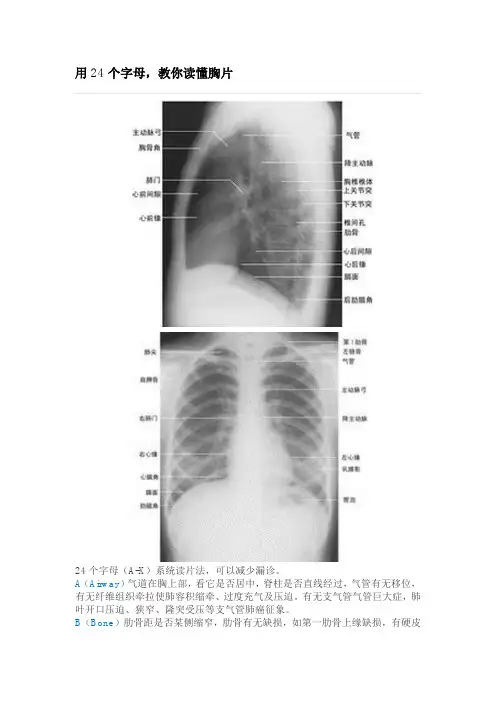

24个字母(A-X)系统读片法,可以减少漏诊。

A(Airway)气道在胸上部,看它是否居中,脊柱是否直线经过,气管有无移位,有无纤维组织牵拉使肺容积缩牵、过度充气及压迫。

有无支气管气管巨大症,肺叶开口压迫、狭窄、隆突受压等支气管肺癌征象。

B(Bone)肋骨距是否某侧缩窄,肋骨有无缺损,如第一肋骨上缘缺损,有硬皮病、类风湿性关节炎的可能。